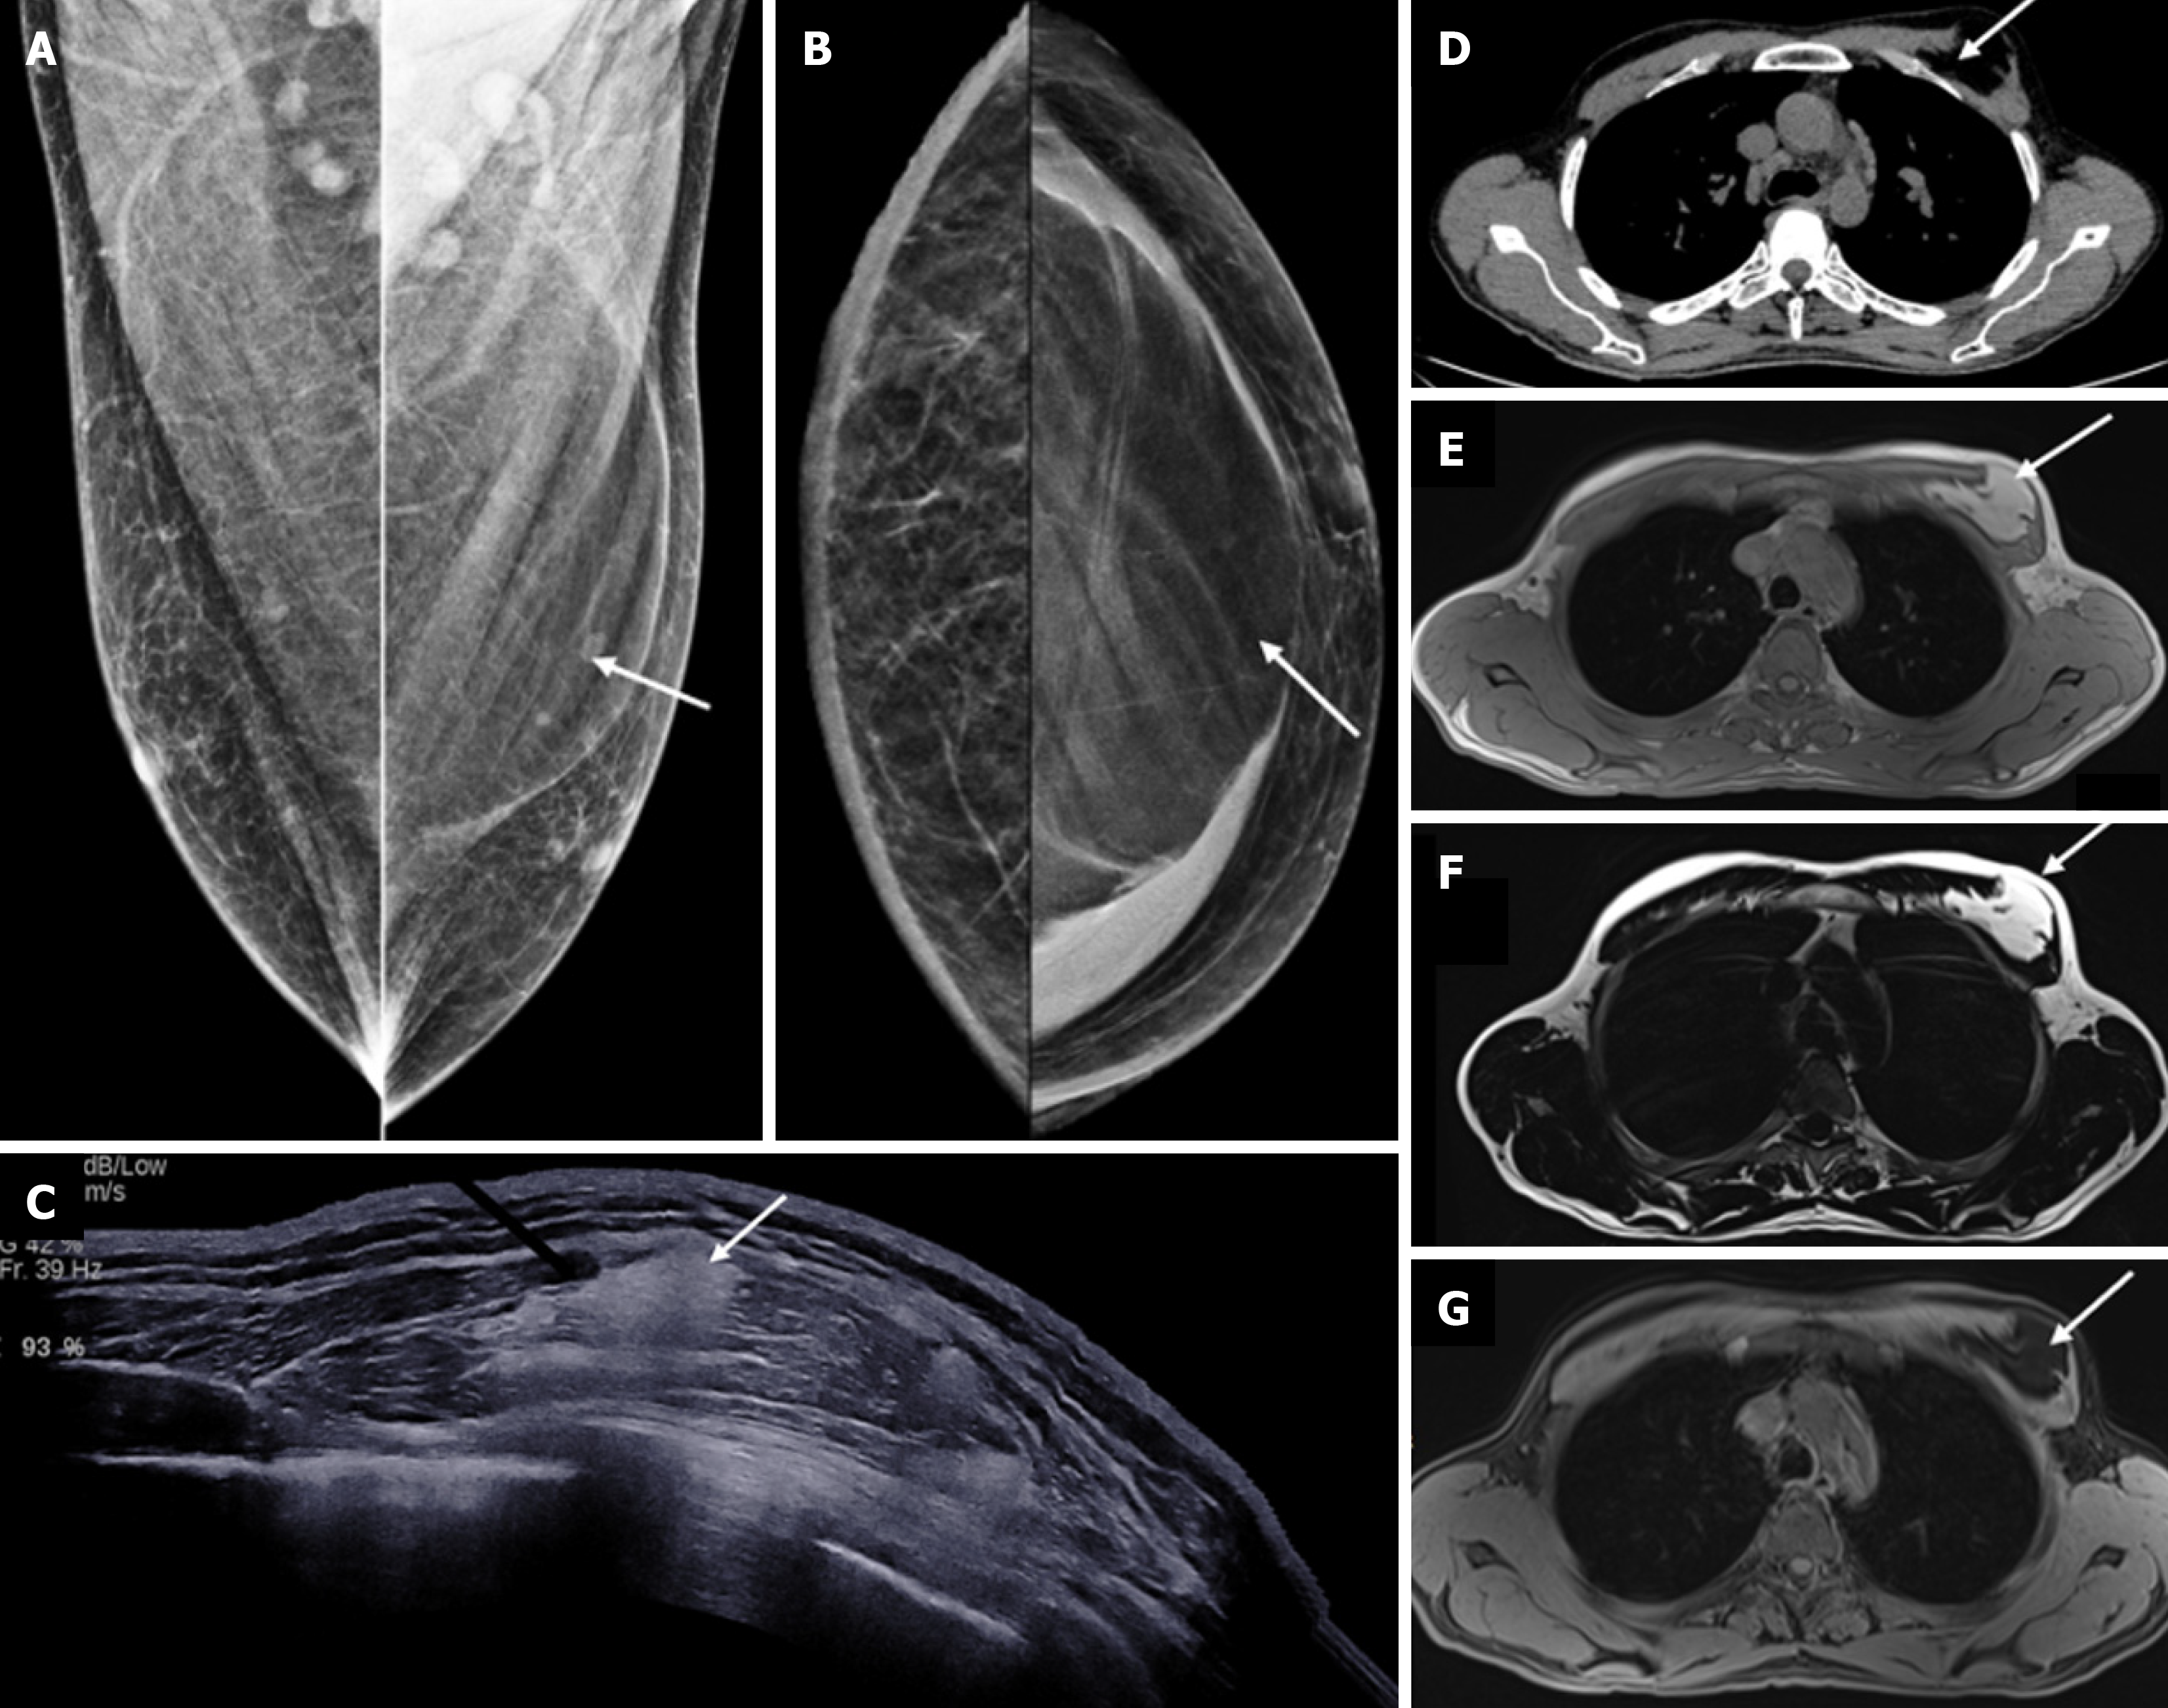

Figure 16  Myofibroblastoma in a 56-year-old male with a palpable mass in the right breast.

A: Ultrasound image showing a round circumscribed heterogeneously hypoechoic mass; B: Axial; C: Sagittal noncontrast computed tomography sections demonstrating a well-defined hypoattenuating soft tissue density mass in the right breast (white arrows) with no calcifications or chest wall invasion.